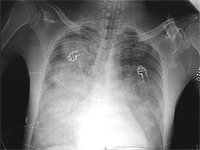

A 38 yo AAF prisoner was seen in the infirmary for a nonproductive cough. She had a history of a URI 2 months previously. Her symptoms associated with the URI had resolved except for the cough. She felt slightly feverish intermittently but her temperature was never documented. She noticed very mild fatigue and DOE that she had attributed to the URI. She was treated with a course of azithromycin without much improvement. A PPD was placed and was interpreted as negative. Because her cough persisted and she had lost 8 pounds she was referred for evaluation. Additional history revealed that her SOB and fatigue probably predated the URI, but was otherwise unremarkable. Physical exam revealed T 100.3, R 28, P 94, BP 150/96; HEENT unremarkable; Lungs with scant bibasilar rales; CV with RRR, nl S1S2, +S4, without murmurs; Extremities without clubbing, cyanosis, or edema. Laboratory data: Hct 41.2, LDH 943; ABG- 7.48/32/58; PFTs: FVC 2.62 L (71% predicted); FEV1 2.23 L (72% predicted); TLC 3.96 L (76% predicted); and DLCO 16.2 ml/min/mmHg (57% predicted).

CXR showing bilateral lower lobe infiltrates

CT showing “crazy paving pattern in lower loges

Diagnosis: Alveolar Proteinosis